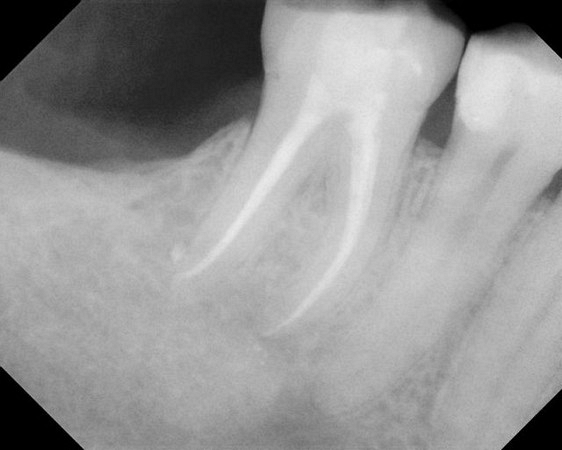

See xrays of before and after a root canal is completed below